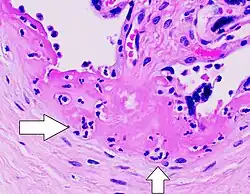

Gross pathology of severe intervillositis, with dark red and soggy tissue. | |